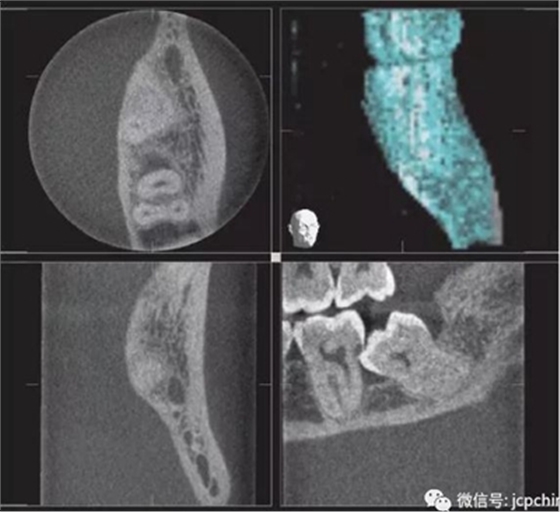

(3)部分容積效應(yīng)產(chǎn)生的偽影

如果探測(cè)器中一個(gè)高對(duì)比度物體的體積小于體素尺寸,則該對(duì)象將會(huì)有效地填充入整個(gè)體素,使其看起來(lái)比實(shí)際物體大。牙膠周邊碎片的顯影就是其中一個(gè)很好的例子,如果牙膠周邊碎片的體積小于體素大小,則圖像上會(huì)看起來(lái)比實(shí)際的大。